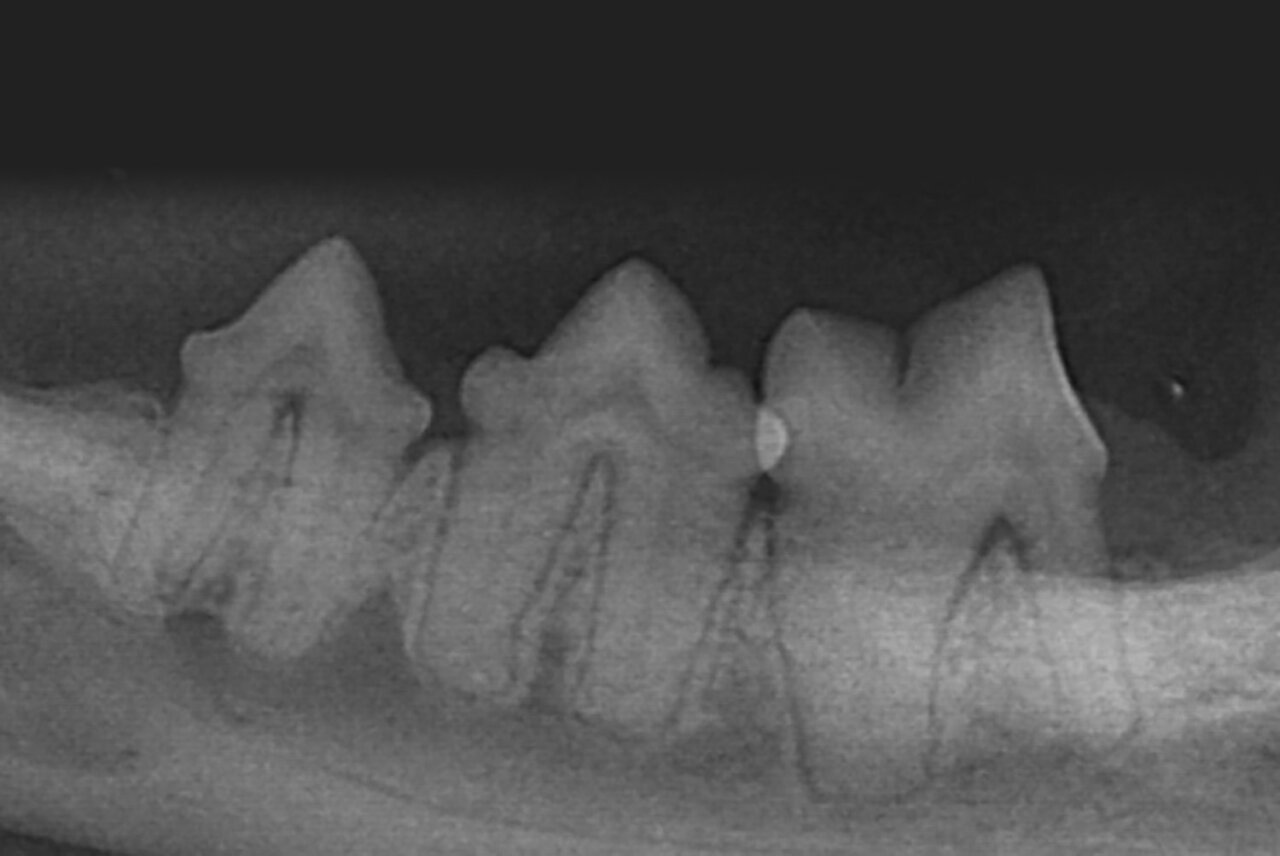

- Técnica paralela: el captador se coloca paralelo al diente y el haz de rayos X se proyecta perpendicular al mismo (imagen 3). Esta colocación solo puede llevarse a cabo con los dientes premolares y molares de la mandíbula.